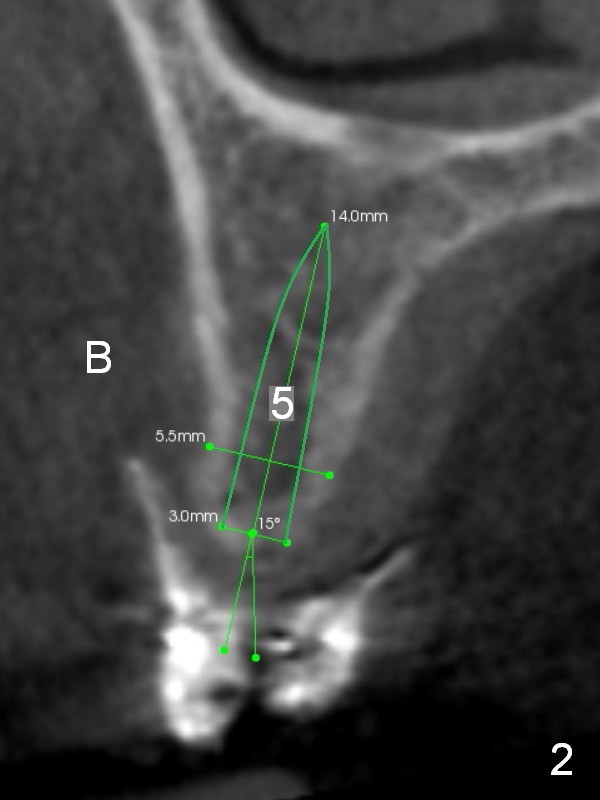

The ridge of the upper right posterior region is variable: narrow at the sites of #4 and 5 (Fig.2,3) and wide at #2 and 3 (Fig.4,5). One-piece implants are going to be placed at the premolars, while wide and extra wide implants at the molars.